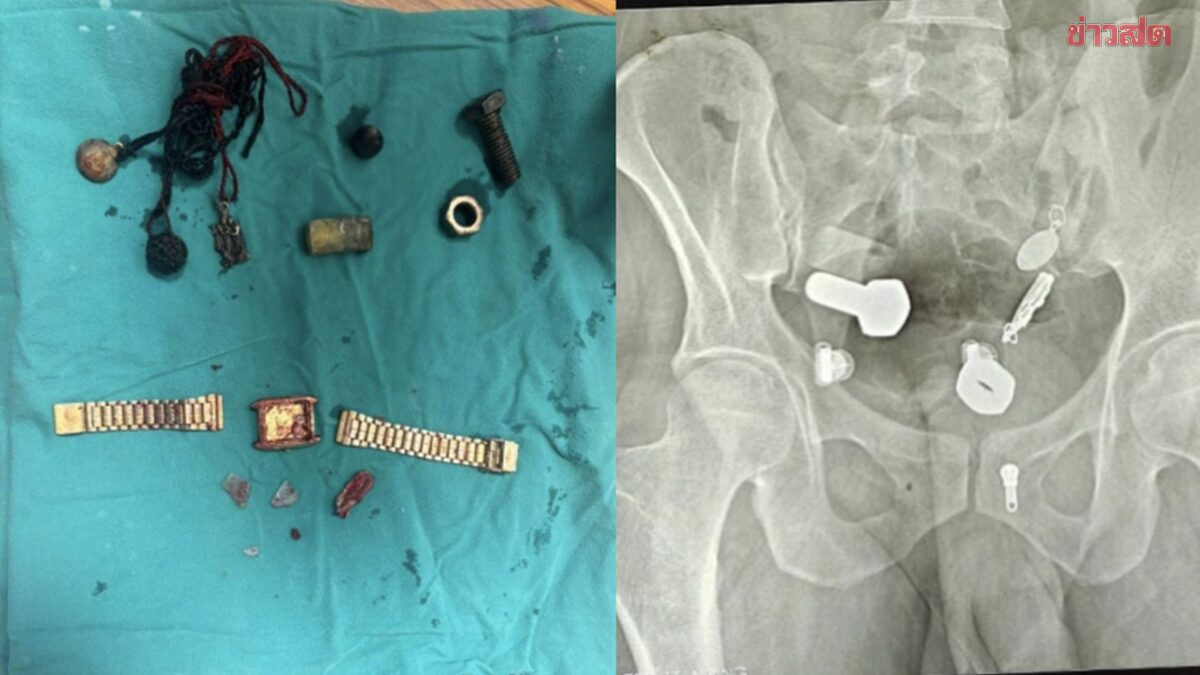

Các bác sĩ đã vô cùng kinh ngạc khi phát hiện một chiếc đồng hồ và vô số ốc vít trong bụng anh ta. Ca phẫu thuật kéo dài ba giờ.

Các bác sĩ đã cố gắng sử dụng ống nội soi để lấy vật thể ra nhưng không thành công, sau đó phải tiến hành một cuộc phẫu thuật lớn kéo dài hơn ba giờ để lấy toàn bộ dị vật ra khỏi cơ thể.

Theo Khaosod, đội ngũ y tế "sốc ngang" khi thấy nhiều vật thể, bao gồm cả một chiếc đồng hồ đeo tay trong bụng nam bệnh nhân. Sau phẫu thuật vài ngày tình hình sức khỏe bệnh nhân đang hồi phục tốt.